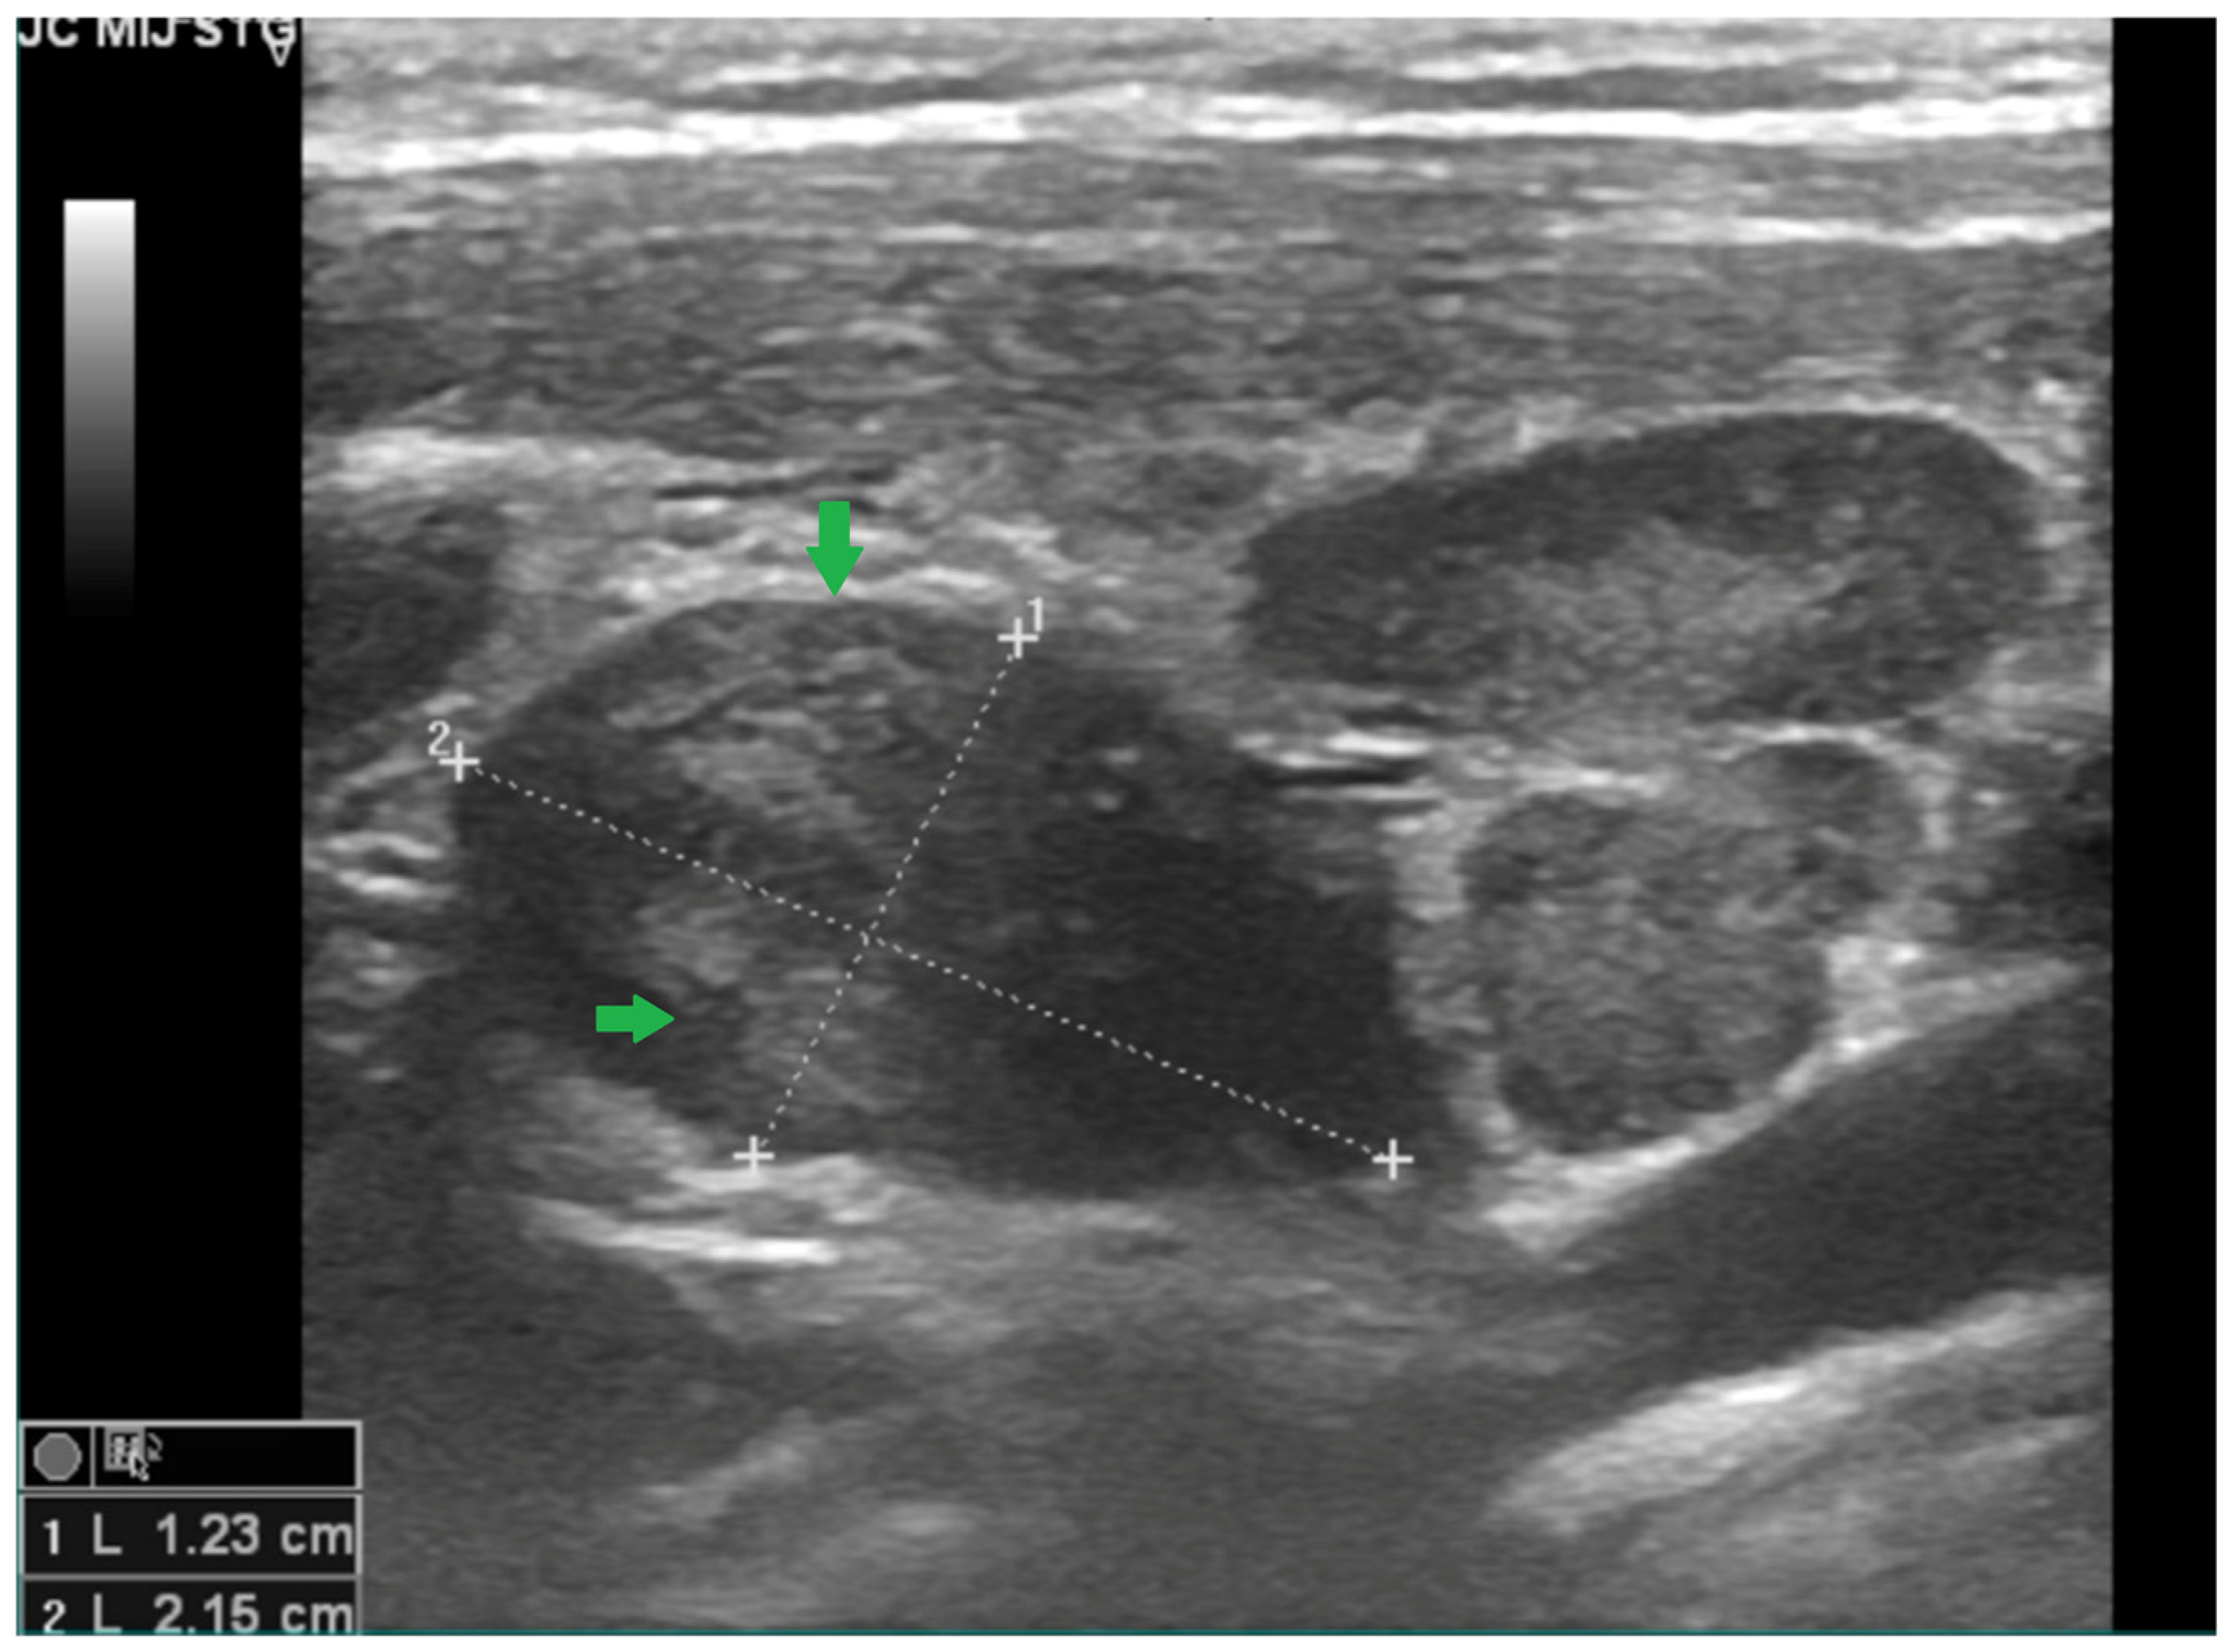

2.2. Case 2